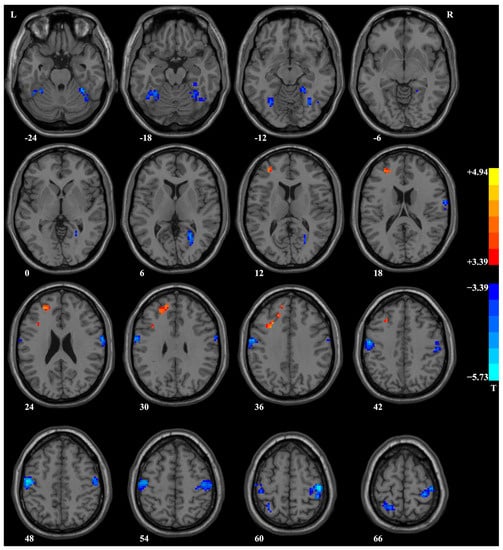

| Cluster Location | Peak (MNI) | Number of Voxels | T Value | p | df | Cohen’s d | ||

|---|---|---|---|---|---|---|---|---|

| x | y | z | ||||||

| Patients with PD at baseline versus controls | ||||||||

| Right postcentral/precentral gyrus | 51 | −18 | 42 | 253 | −3.39 | <0.001 | 106 | −0.65 |

| Left postcentral/precentral gyrus | −57 | −6 | 48 | 220 | −3.39 | <0.001 | 106 | −0.65 |

| Right fusiform gyrus/cerebellum VI | 18 | −45 | −12 | 121 | −3.39 | <0.001 | 106 | −0.65 |

| Left superior/middle frontal gyrus | −27 | 45 | 21 | 88 | 4.43 | <0.001 | 106 | 0.85 |

| Left fusiform gyrus/cerebellum VI | −30 | −48 | −24 | 85 | −3.40 | <0.001 | 106 | −0.65 |

| Right calcarine/lingual gyrus | 27 | −57 | 9 | 58 | −3.42 | <0.001 | 106 | −0.66 |

| Right postcentral gyrus | 63 | −6 | 33 | 53 | −3.40 | <0.001 | 106 | −0.65 |

| Left superior parietal lobule | −15 | −57 | 66 | 44 | −3.41 | <0.001 | 106 | −0.66 |

| Left middle/inferior frontal gyrus (triangular part) | −30 | 15 | 33 | 38 | 4.94 | <0.001 | 106 | 0.95 |

| Patients with PD after 4-week treatment versus at baseline | ||||||||

| Left fusiform gyrus | −30 | −45 | −9 | 41 | 4.57 | <0.001 | 35 | 1.08 |